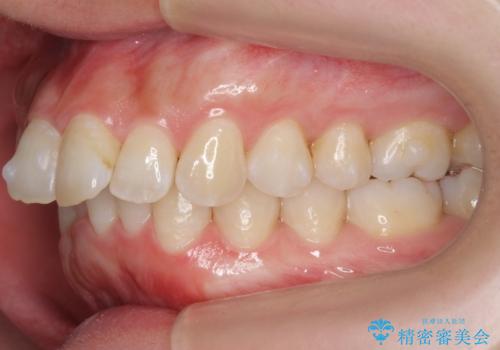

前歯をさげたい 歯を抜かずに マウスピース矯正で治したい

- 上の前歯が出ているとのことで来院。

歯を抜かずに、上の奥歯を後ろにさげつつ上の前歯を小さく少し削る処置を行い前歯の角度を修正しました。

右上下の奥歯もすれ違い咬合も、治療で改善しています。

下の前歯が生まれつき3本でしたので上下の正中は合わない仕上がりとなります。